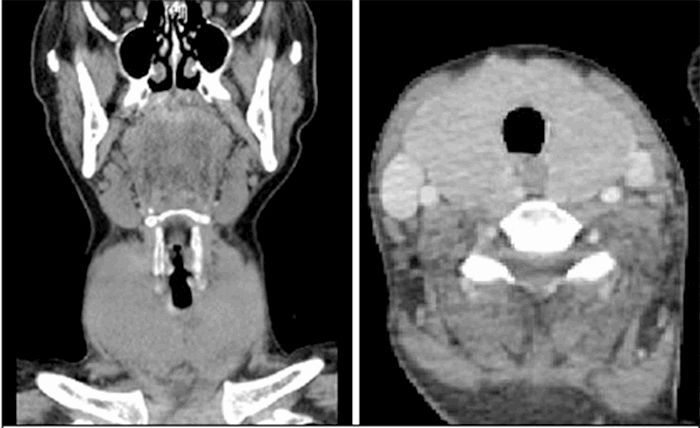

A 32-year-old woman presented as a second-level trauma activation after falling down 14 stairs at home with loss of consciousness and was found down by her significant other. On arrival, she was tachycardic to the 130s and hypertensive to the 180s with a sole complaint of right knee pain. The patient was evaluated and sent immediately for CT scans as a part of her trauma workup. CT brain and cervical spine were unremarkable. CT chest abdomen pelvis with IV contrast revealed diffuse thyroid enlargement and lymphadenopathy (Figure 1).

Figure 1. Diffuse thyroid enlargement with lymphadenopathy.